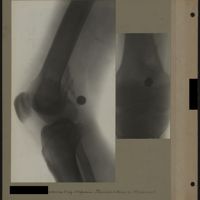

0070 - Page 66 - [Radiographies du genou]0070 - Page 66 - [Radiographies du genou]